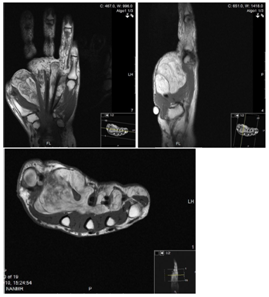

A 60year-old female secretary presented with swelling on the dorsal and volar aspects of her left non-dominant distal forearm and a mild ache at the base of the thumb. The lesion was non-tender and mobile, causing no functional impairment. Past medical history included hypercholesterolaemia, hypertension, gastroesophageal reflux and allergic rhinitis and easy bruising was reported. Ultrasound confirmed a well-defined, hyperechoic lesion, avascular on colour flow imaging, consistent with an intramuscular lipoma.MRI confirmed a 4x2.5x5.5cm lobular fatty tumour of the distal forearm, bridging the anterior and posterior compartments (Figure 3), extending to the distal radioulnar joint, close to the interosseous nerve. Fine-needle aspiration cytology demonstrated benign spindle and epithelioid cells. The possibility of a benign fibrohystiocytic tumour, or low-grade malignancy was raised and synovial sarcoma thought unlikely. Surgical exploration under was performed via a volar approach. A lipomatous lesion deep to the flexor tendons displaced the ulnar artery and nerve. The lesion penetrated the interosseous membrane, which required division for en masse excision. Histopathology reported a benignlipoma. A full functional recovery was noted, no recurrence at two years.

Figure 3 Axial T1 MR Image of the left forearm demonstrating the mass of lipoma crossing the interosseous membrane between radius and ulna.